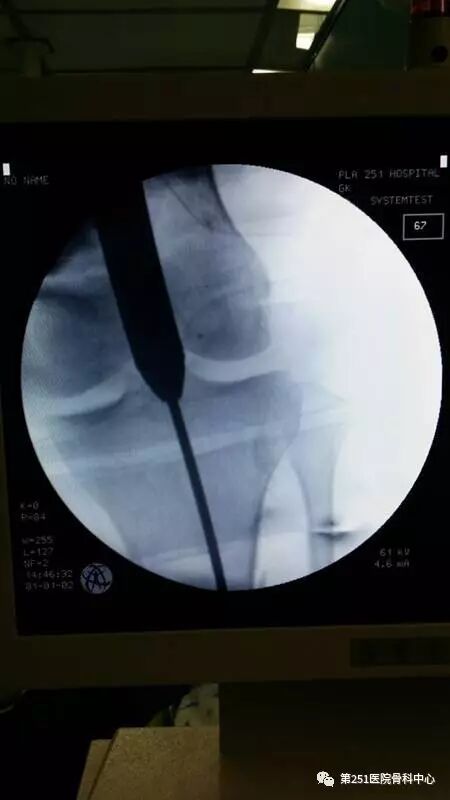

病例6:男性,39岁,车祸伤SchatzkerⅥ型胫骨平台骨折。

![]()